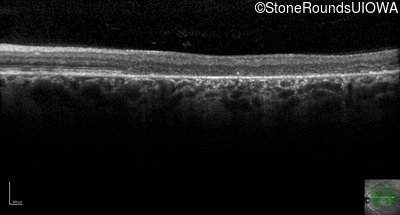

Optical Coherence Tomography - Left - 20/200

Exemplar / OCT Stack